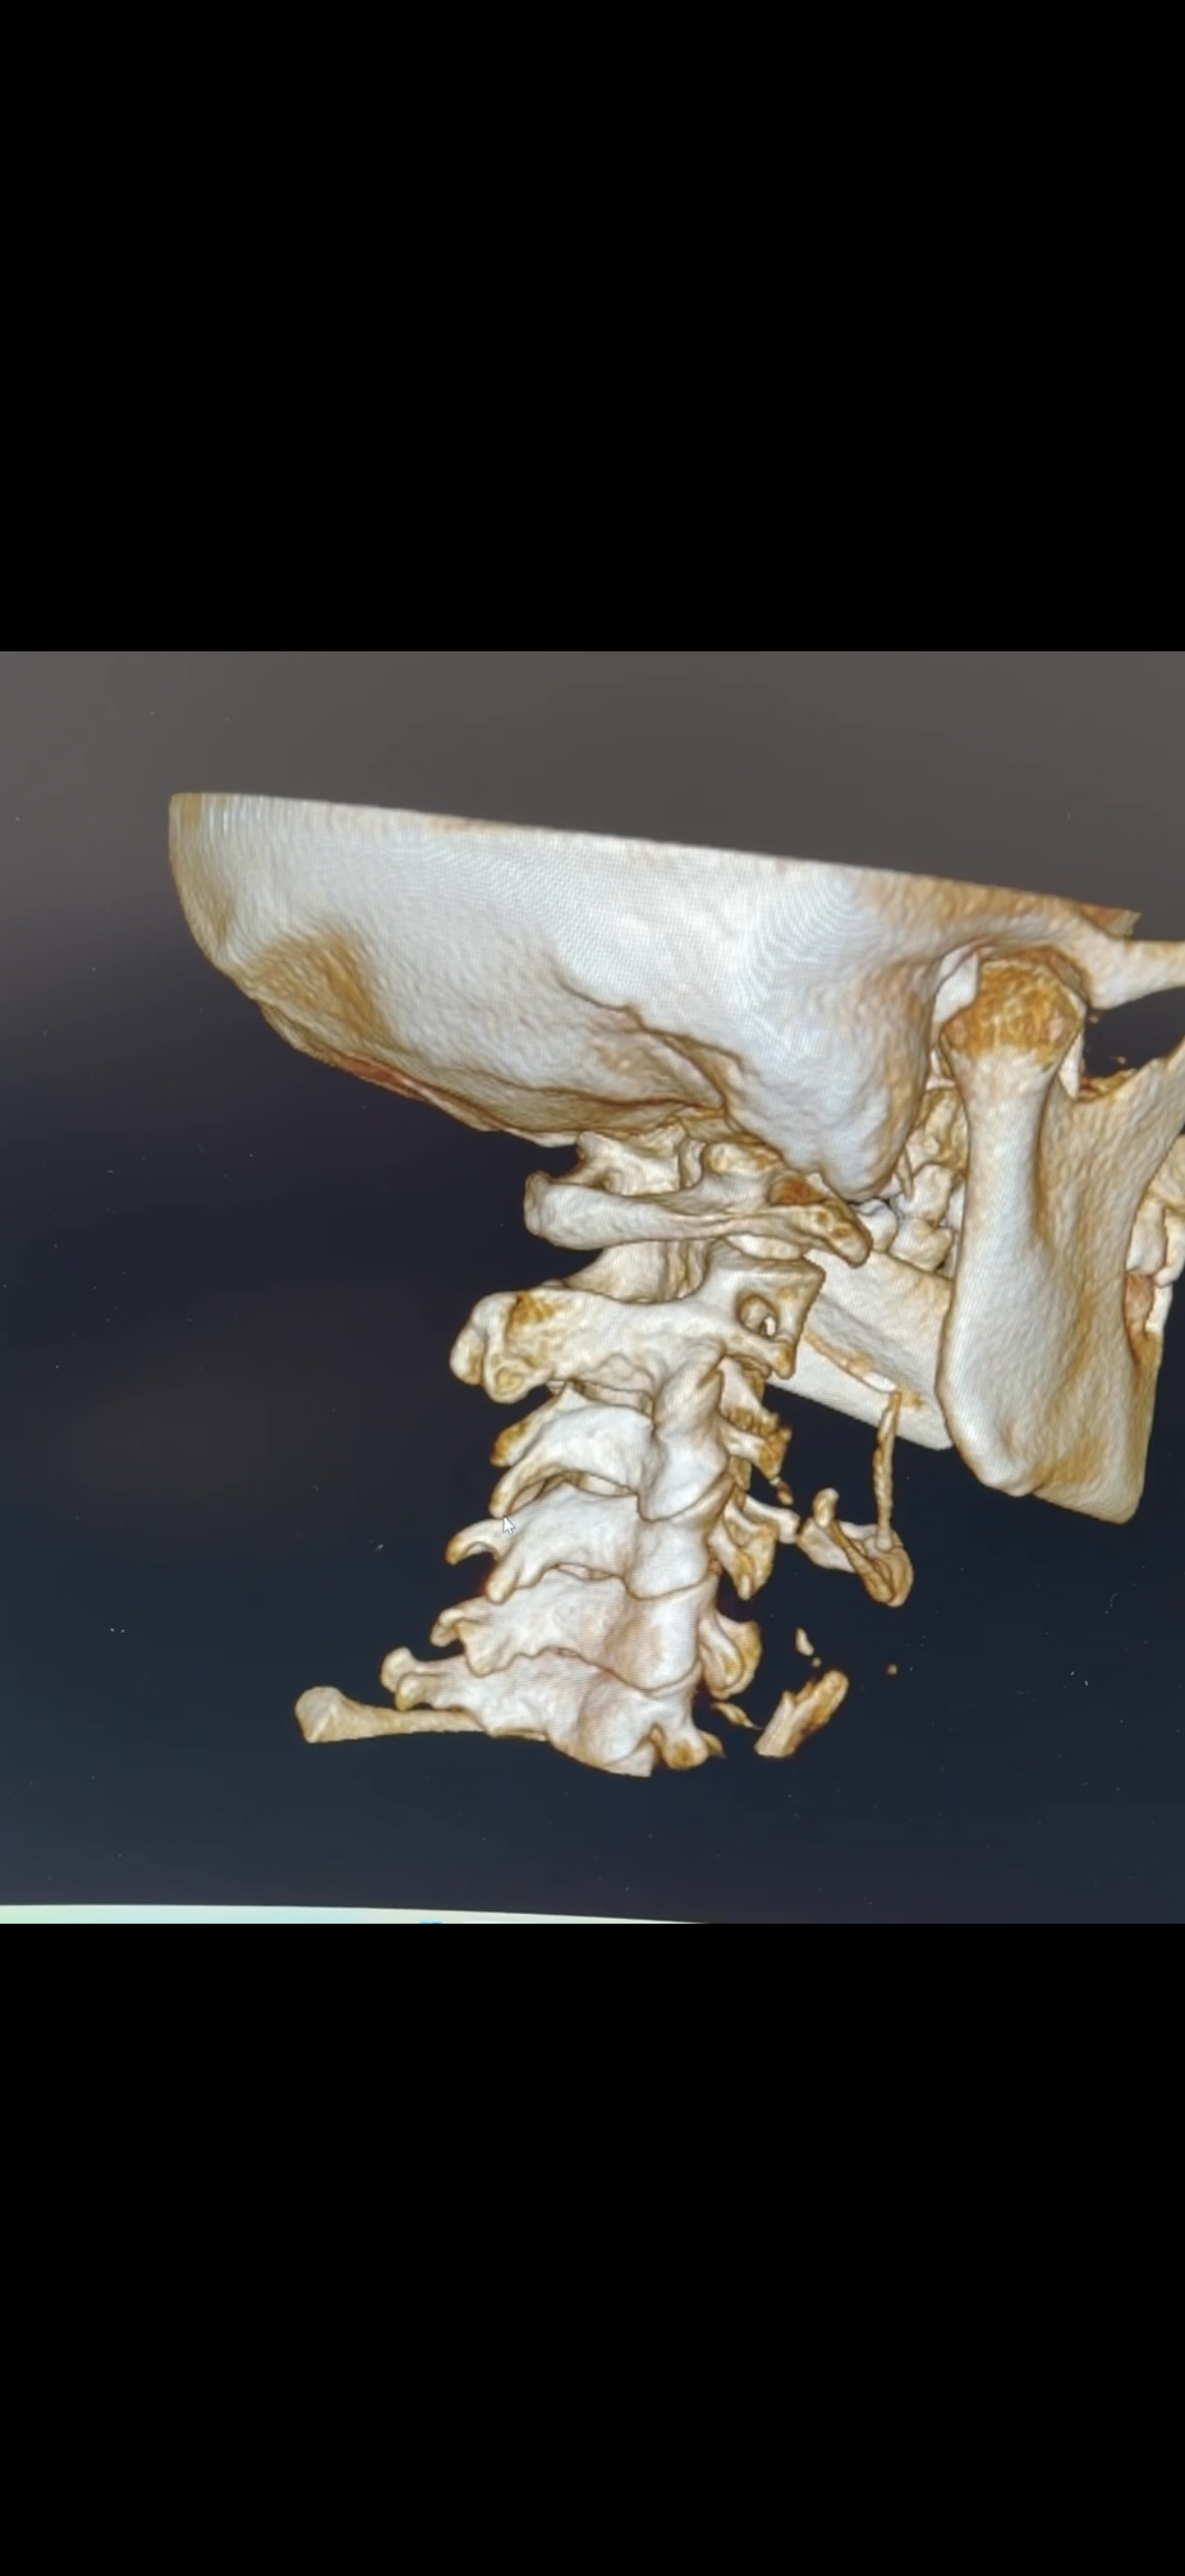

Hypermobility and the Upper Cervical Spine: Understanding the Connection

Hypermobility affects joint stability, proprioception, and muscle tension—especially in the upper cervical spine. This post explains the difference between general hypermobility and EDS, why the atlas and axis are so important, and how gentle, precise upper cervical care can support long-term stability and function.